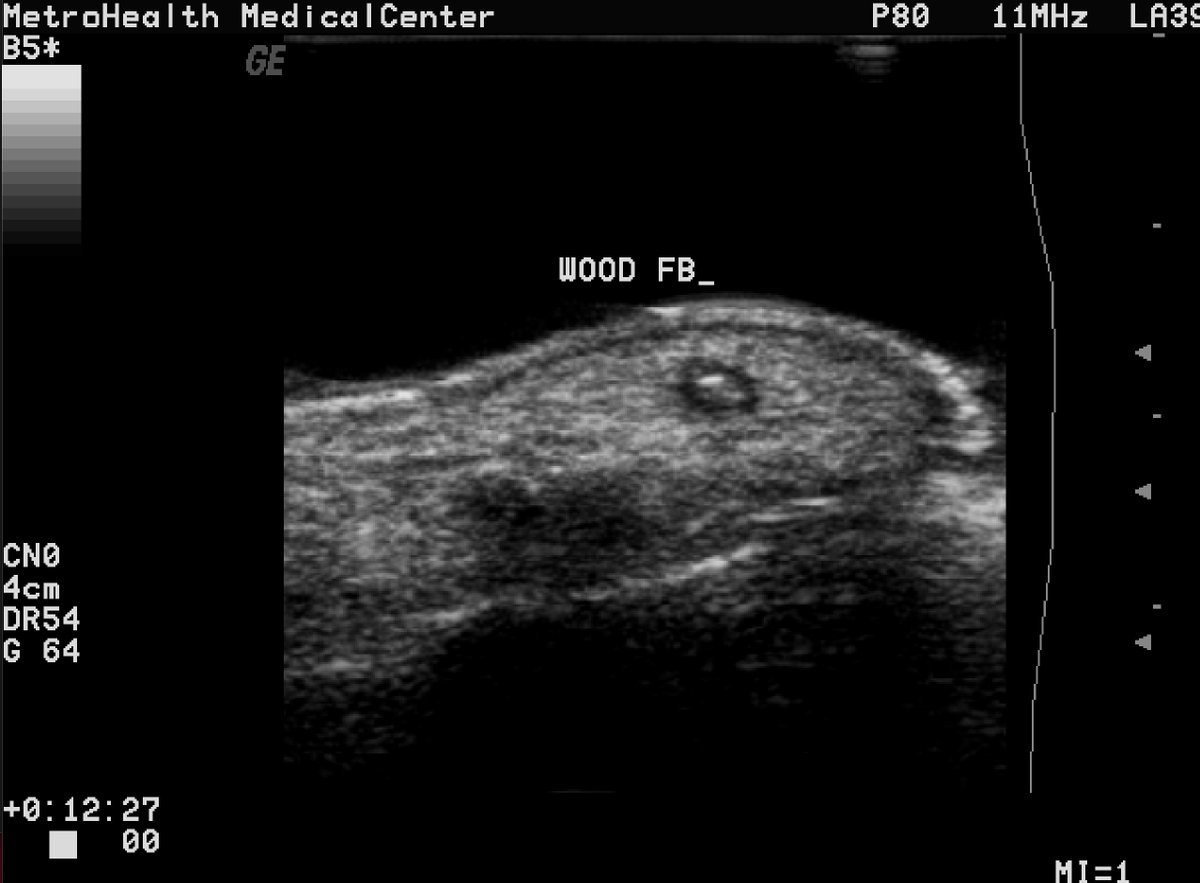

Retained wood splinter with halo seen. Same case from above where removal shown. Standoff pad used.

Retained wood splinter in heel with posterior shadowing seen. Injury happened one day ago. Standoff pad used.